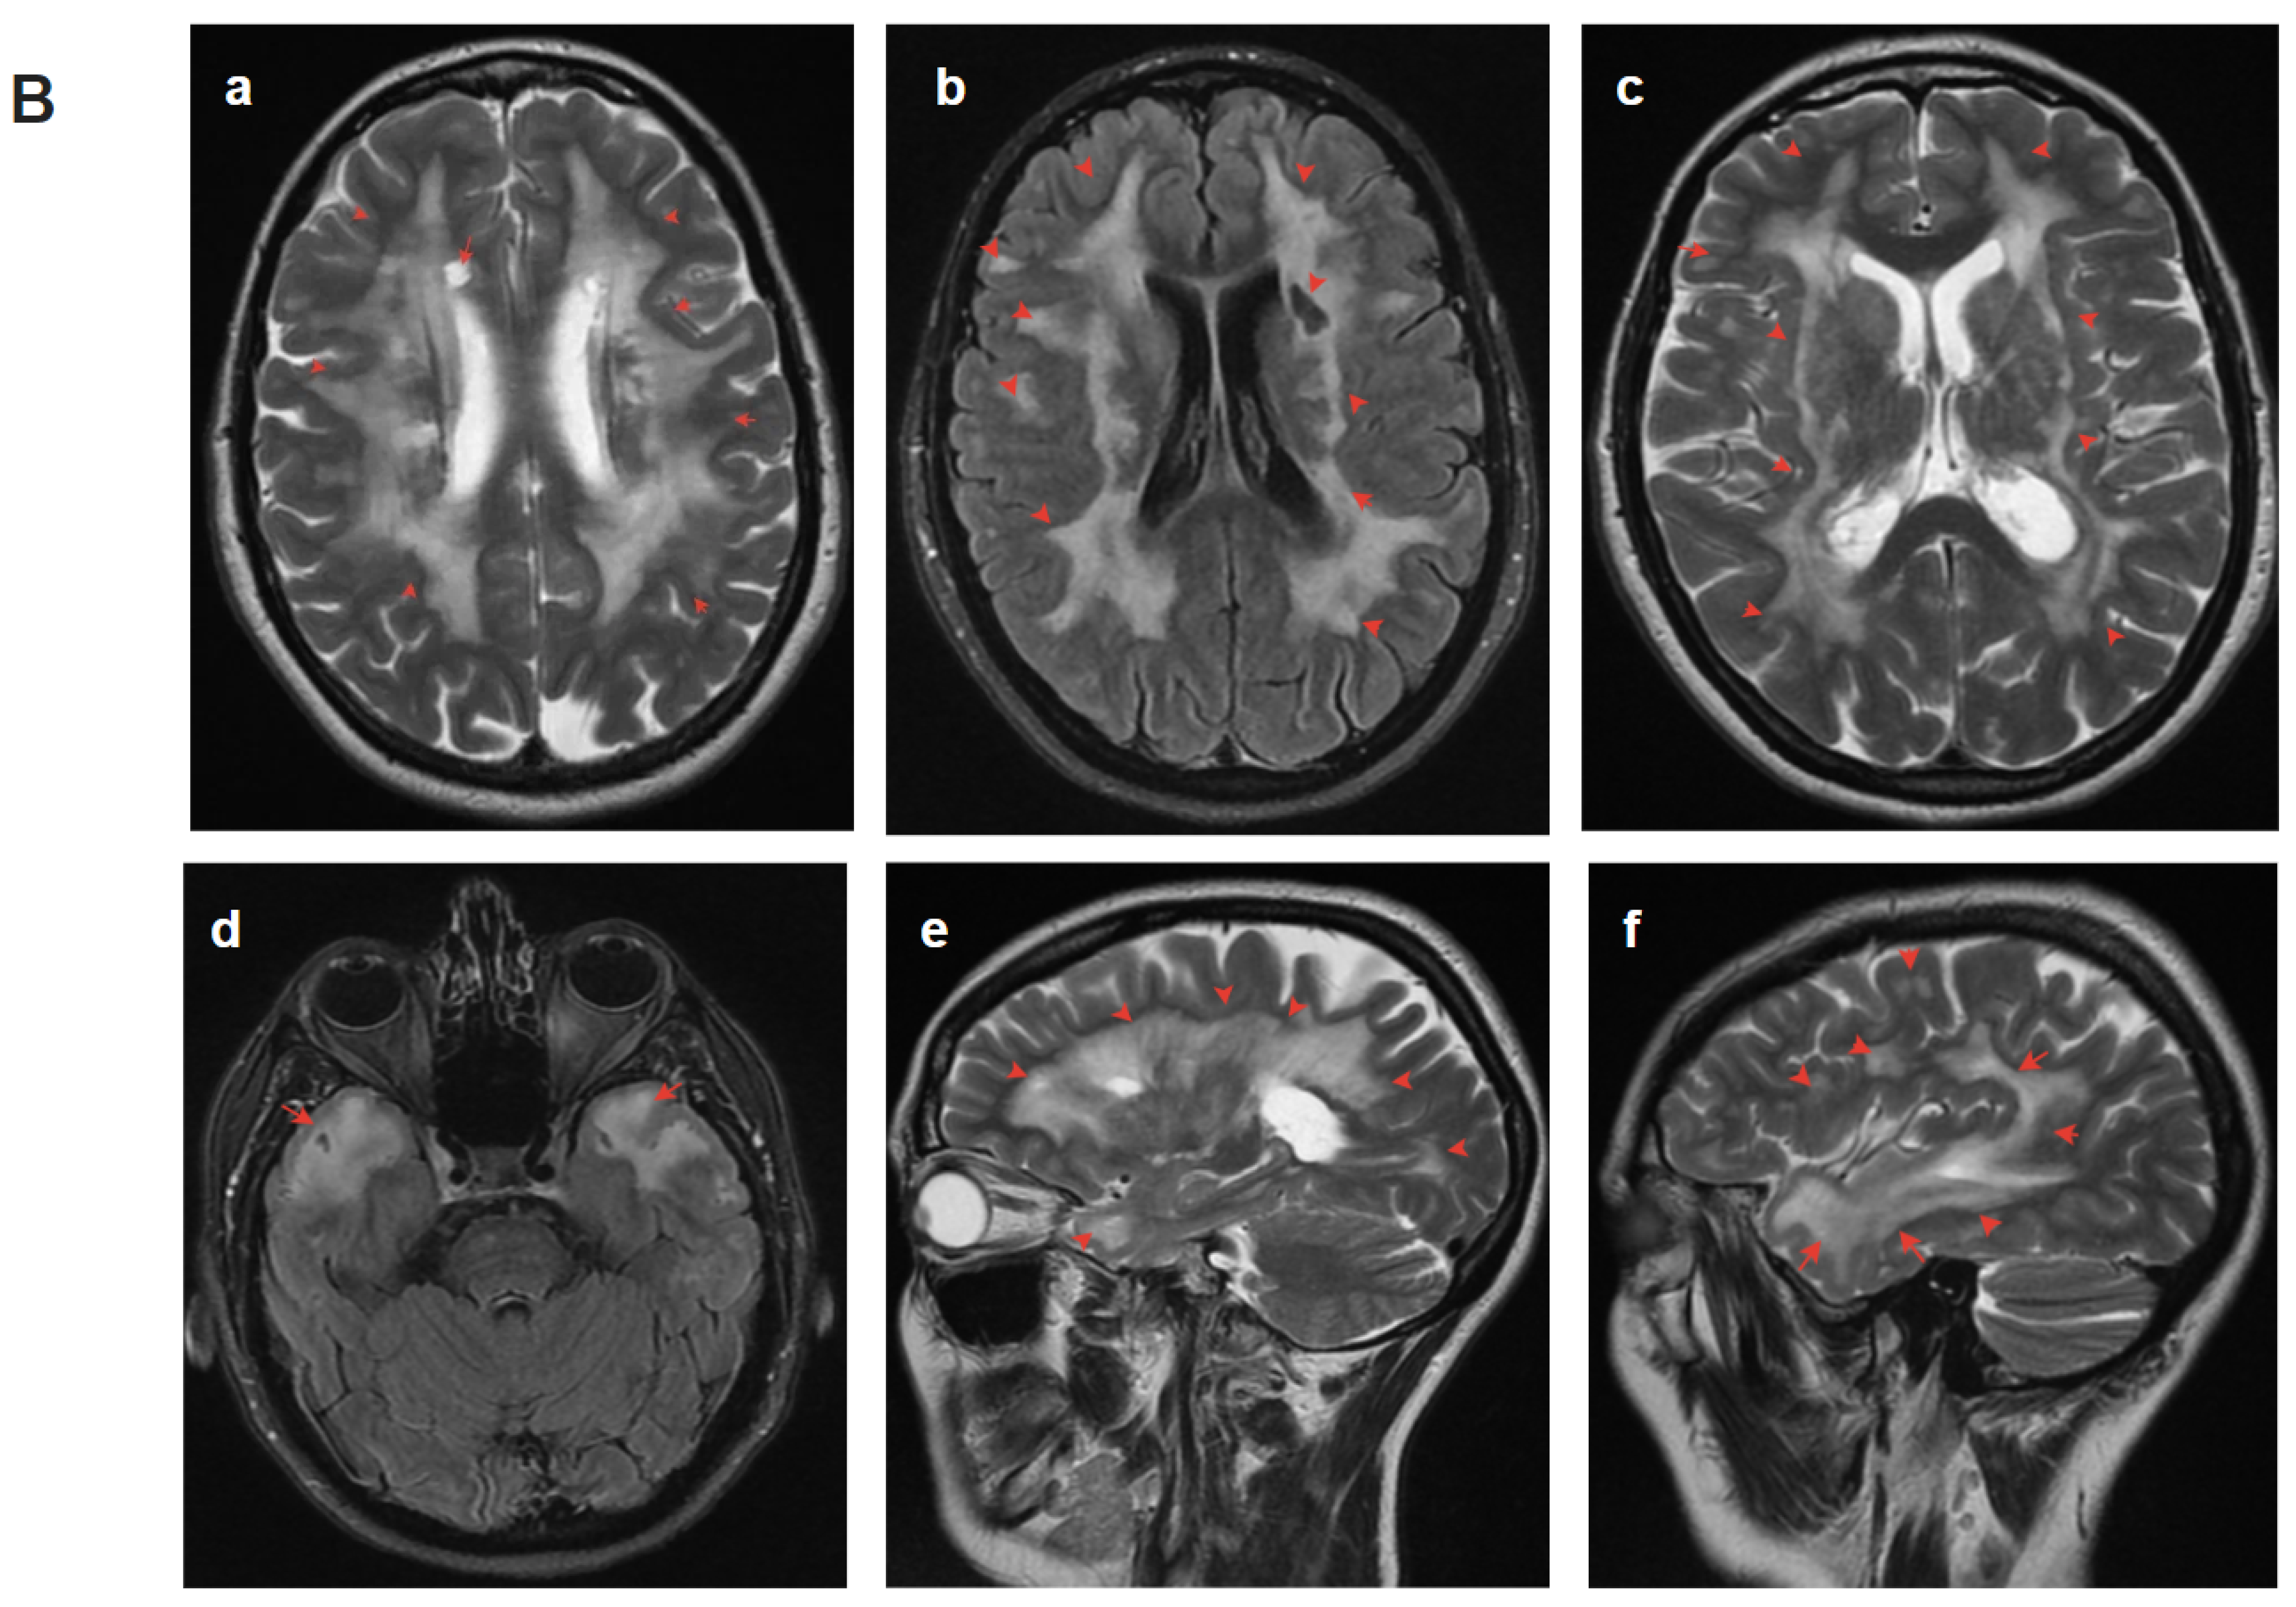

2.4.1. Patient 1